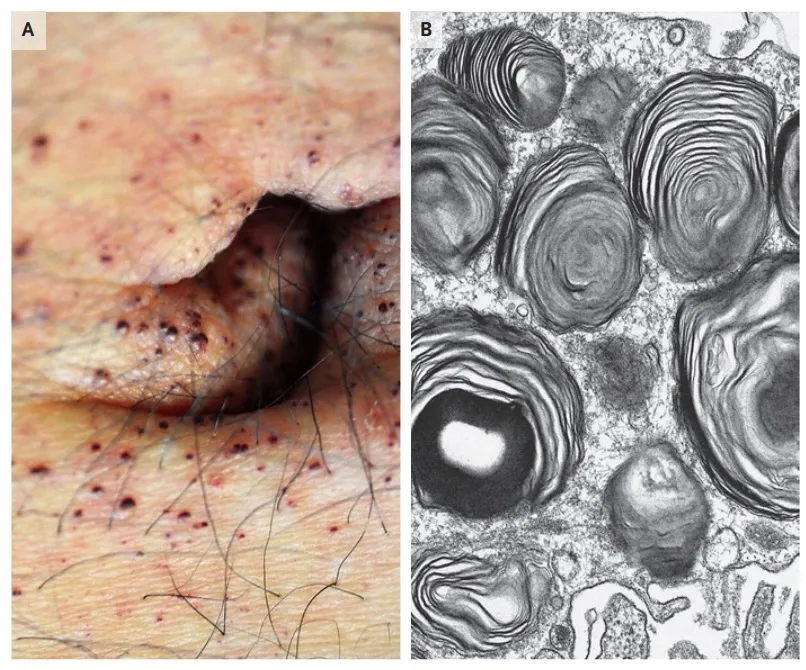

DRC “indeterminada” raramente é falta de diagnóstico — quase sempre é falta de método. Tempo de evolução, urina bem avaliada, USG renal e história clínica dirigida mudam conduta e evitam erros comuns na prática nefrológica.